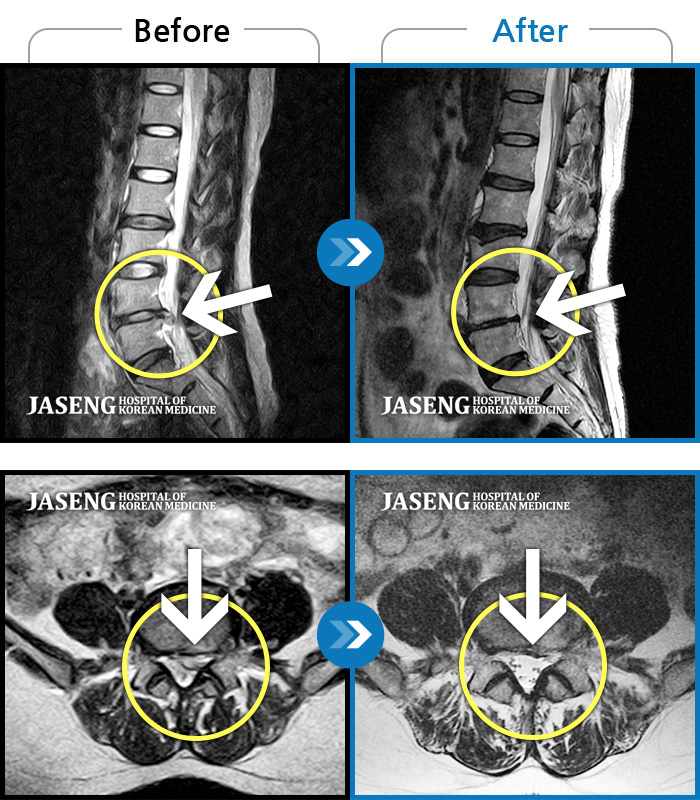

허리디스크

수원 · 김태성 원장

허리 통증과 좌측 대퇴부 저림과 당김

촬영시기

2023.02.03 ~ 2024.02.14

2024.11.21